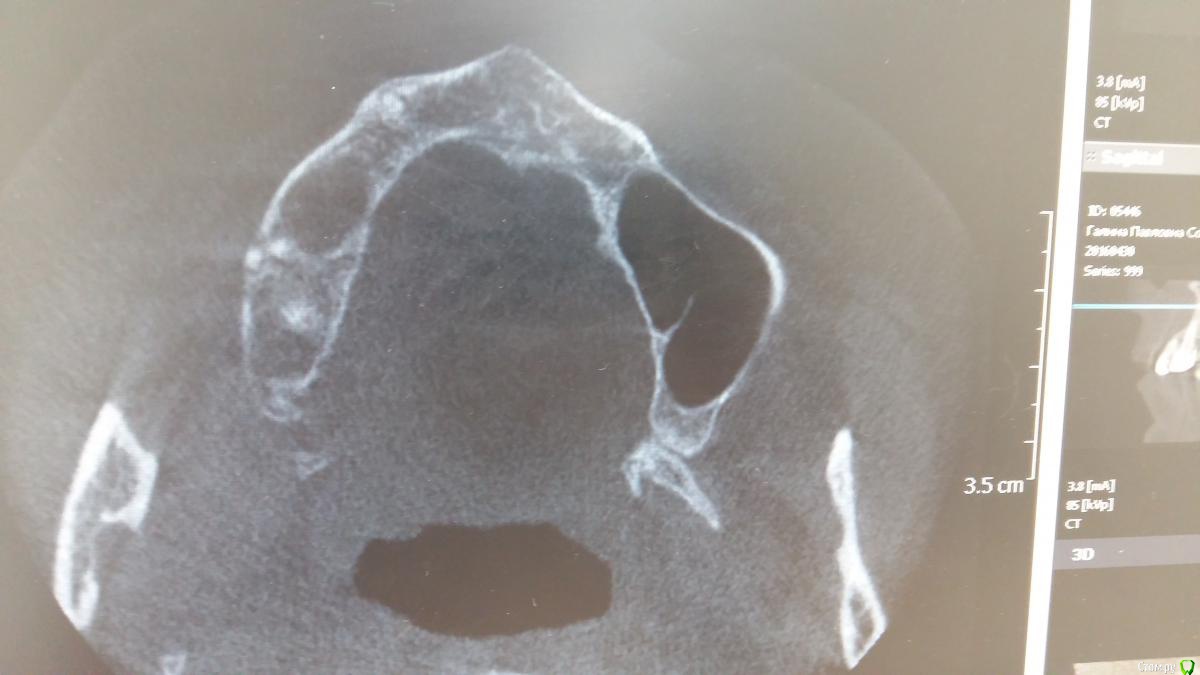

Zubnik7 Опубликовано 30 сентября, 2016 Автор Поделиться Опубликовано 30 сентября, 2016 Перегородка не полная,сейчас выложу новые срезы,более информативные Ссылка на комментарий

Zubnik7 Опубликовано 30 сентября, 2016 Автор Поделиться Опубликовано 30 сентября, 2016 Новые срезы Ссылка на комментарий

Konrad Опубликовано 7 октября, 2016 Поделиться Опубликовано 7 октября, 2016 Подскажите варианты проведения синус лифтинга,корень удаленЯ бы делал !не большое! окно аккурат в проекции перегородки. Не подламывать её во внутрь, а на против снимать . Выйдет легкл с частью перегородки. За счёт не большого окна получите либо мембрану без изъян, либо точечный прокол, либо не большую перфорацию. Но главное в лохмотья ничего не порвется. Потом уже формируется нормальное окно в соответствии с размером вмешательства.Это позволит без проблем отслоится и либо ушить её, либо просто проложить коллагеном. Ссылка на комментарий